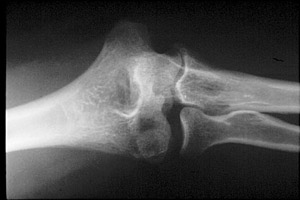

Capitellum Fracture

Fractures of the capitellum are the result of direct trauma to the extremity. In pediatric patients, this site is the second most common site of injury about the elbow.

- Click on the image for a larger versionBAP radiograph of the elbow. This shows the fracture of the capitellum.